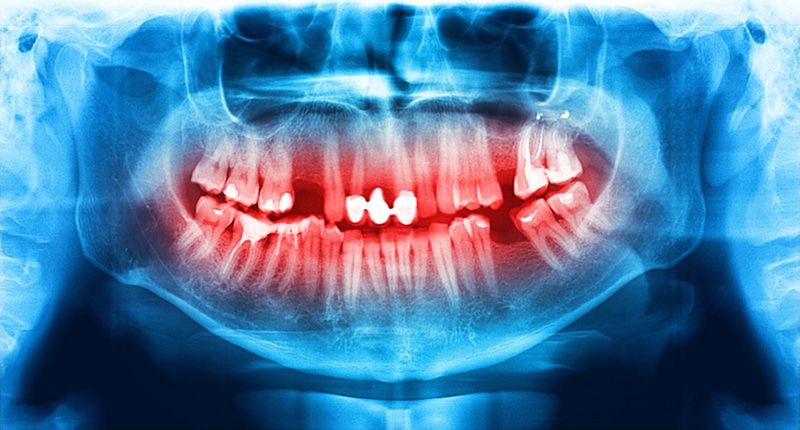

Панорамный снимок (или ортопантомограмма) – это плоское двухмерное изображение челюстей, зубов, гайморовых пазух и даже височно-нижнечелюстного сустава. Поскольку поверхность челюстей изогнутая, на плоской рентгеновской плёнке снимок отображается неравномерно увеличенным в боковых и передних отделах челюстей – то есть слегка деформированым.

- Много информации на одном снимке — видны все зубы с корнями, обе челюсти, гайморовы пазухи, височно-нижнечелюстные суставы, частично даже полость носа.

- Двухмерный вид не даёт информацию во всех плоскостях — для этого нужен 3D КТ снимок.

- Недостаточно чёткое отображение мелких деталей.

- Искажения, наслоение теней от других костей и позвоночника, смещения и затемнения неизбежны.

- Лишь ориентировочное представление о размерах корней зубов и расстоянии до важнейших анатомических образований (канал нижнечелюстного нерва и гайморова пазуха), из-за того, что изображение растянуто неравномерно в боковых и передних отделах.

Что видно на панорамном снимке?

- он демонстрирует состояние всех без исключения зубов на нижней и верхней челюсти, а также состояние гайморовых пазух и височно-нижнечелюстного сустава;

- с помощью него доктор может увидеть зачатки постоянных зубов у малышей и обнаружить возможные патологии их развития;

- ортопантомограмма информирует о кариозных очагах, гранулемах и кистах, ретинированных «зубах мудрости»;

- с помощью нее можно определить заболевания пародонта и костной ткани еще на ранних этапах;

- врач получает максимум информации для проведения коррекции, протезирования и дентальной имплантации;

- панорамный снимок позволяет проверить качество проведенного лечения, в частности, пломбирования корневых каналов.